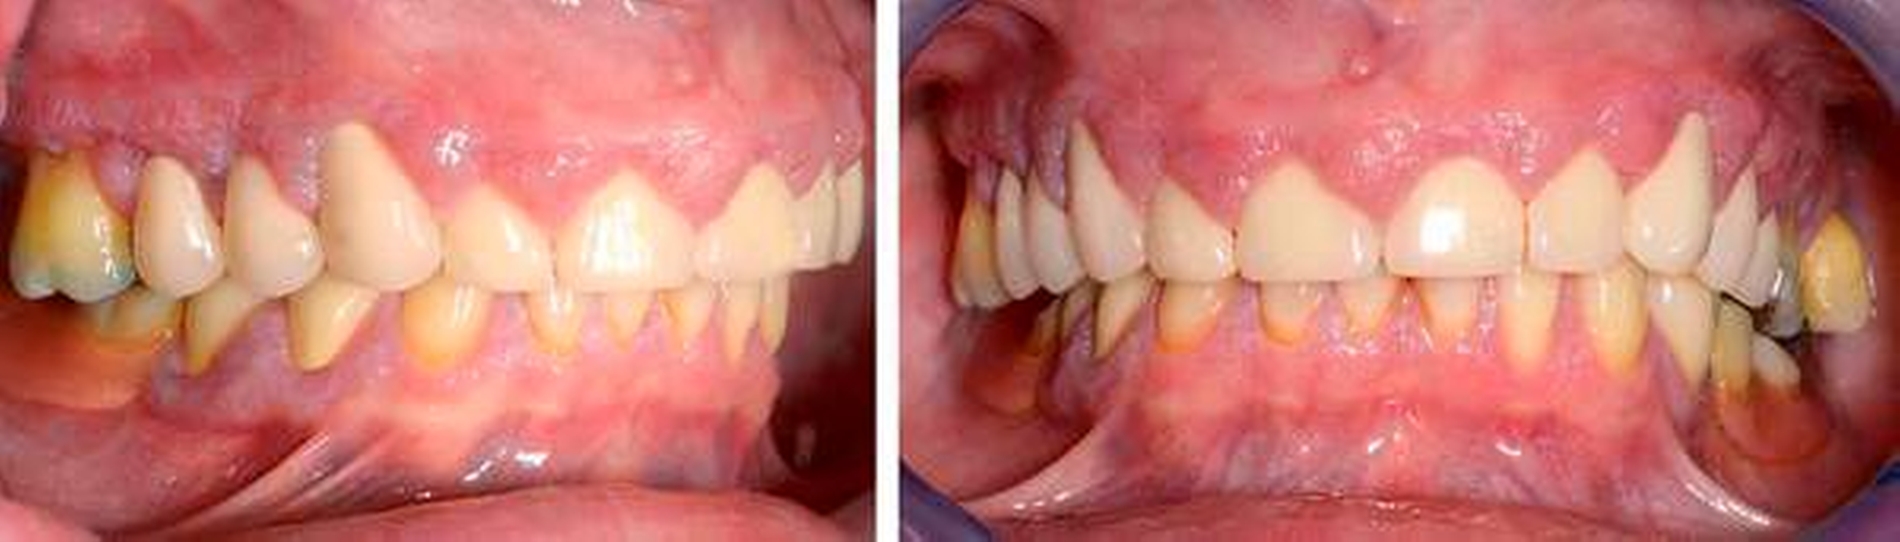

Befund: Bei der klinischen Untersuchung zeigten sich vestibulär und oral im Bereich der Papillen und der befestigten Gingiva generalisierte Gingivawucherungen im Oberkiefer (OK) und im Unterkiefer (UK). Die Interdentalräume waren aufgrund der Gingivawucherungen nicht für Hygienehilfsmittel durchgängig. Der Parodontale Screeningindex (PSI) wies im OK die Codes 3/3/4, im UK die Codes 3/1/3 auf. Der daraufhin erhobene Parodontalstatus (Abbildung 2) zeigte im OK Sondierungstiefen bis 7 mm mit Furkationsbeteiligungen Grad I (Zähne 16, 26, 27). Im UK betrugen die Sondierungstiefen bis zu 4 mm. Die Zahnbeweglichkeit an den Zähnen 16, 26 (Grad I) und 27 (Grad II) war erhöht.

Der Plaqueindex PCR betrug 72 Prozent [O`Leary TJ et al., 1972] und der gingivale Blutungsindex GBI 75 Prozent [Ainamo J et al., 1975]. Das alio loco angefertigte Orthopantomogramm (Abbildung 3) zeigte horizontalen Knochenabbau bis zu einem Drittel der Wurzellänge in beiden Kiefern. Die Zähne 16 und 26 wiesen einen Knochenabbau > 2/3 der Wurzellänge auf. Am Zahn 27 mesial erreichte der Knochenabbau die Wurzelspitze; zudem war der Zahn elongiert und wies eine Kippung nach distal auf. In einer ersten Einzelzahnprognose wurden alle Zähne mit Ausnahme von Zahn 27 als sicher eingestuft. Prothetisch war die Patientin im OK mit einer Brücke (13 bis 15), Kronenblöcken (21/11, 21/22, 24/25) und Amalgamfüllungen an den Zähnen 16 und 26 sowie im UK mit einer geschiebeverankerten Modellgussprothese versorgt.

Sechs Wochen nach Deep Scaling und Root Planing erfolgte eine zweite Reevaluation mit Befunderhebung [MacNeil RL et al., 1999]. Erhöhte Sondierungstiefen lagen nur noch an den Zähnen 27 (5 mm) und 34 (4 mm) vor (Abbildung 4). Die Gingivawucherungen hatten sich vollständig zurückgebildet (Abbildungen 5a bis 5e). Die Plaque- und Blutungsindizes waren niedrig und stabil (20 Prozent). Abschließend wurde eine PZR zusammen mit einer subgingivalen Reinigung an den Zähnen 27 und 34 durchgeführt. Die Prognose der Zähne mit Ausnahme des Zahns 27 ist weiter als sicher einzustufen. Zahn 27 bleibt kritisch. Dies ist durch den Attachmentverlust von 10 mm mesial und den Lockerungsgrad II begründet. Aufgrund der kompromittierenden parodontalen Situation und der eingeschränkten prothetischen Wertigkeit könnte bei Beschwerden an Zahn 27 neben einer chirurgischen Taschenelimination auch eine Extraktion erwogen werden. Die bisherige prothetische Versorgung könnte dann im Konzept einer verkürzten Zahnreihe belassen werden [Fueki K et al., 2015; Levey C et al. 2015]. Da die Patientin vorerst keine weitere Therapie an Zahn 27 wünschte, musste an dieser Stelle von einer chirurgischen Taschenelimination abgesehen und der Zahn belassen werden.